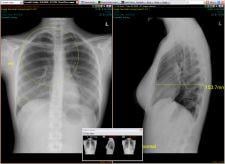

The rural hospital selected NovaPACS because it offered a complete, Web-based PACS that could be installed in less than a month and was affordable.

“Rural hospitals benefit from the Web-based PACS as interpreting physicians have the freedom to access images anytime from any location, not just at the hospitals physical radiology department,“ said Paul Shumway, NovaRad vice president.